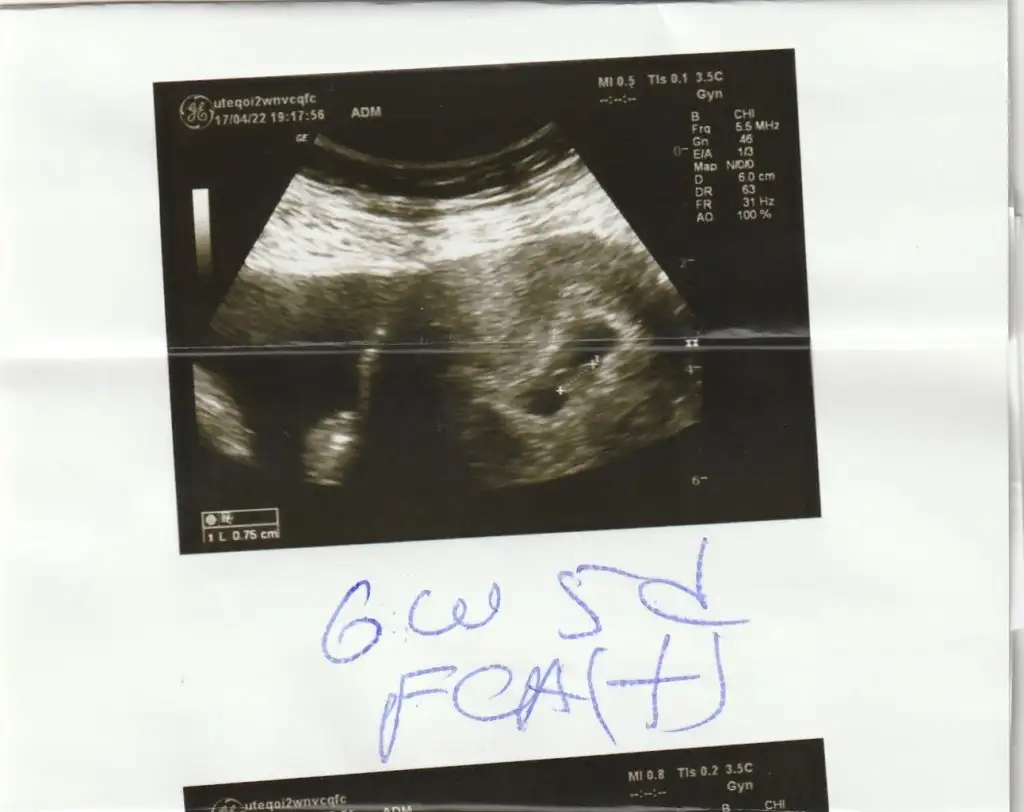

karından mı canımMerhaba bana da yorum yapar mısınız?6+2 haftalıkEki Görüntüle 3051268

Prenses canımMerhaba bana da yorum yapar mısınız?6+2 haftalıkEki Görüntüle 3051268

Merhaba bana da yorum yapar mısınız?6+2 haftalıkEki Görüntüle 3051268